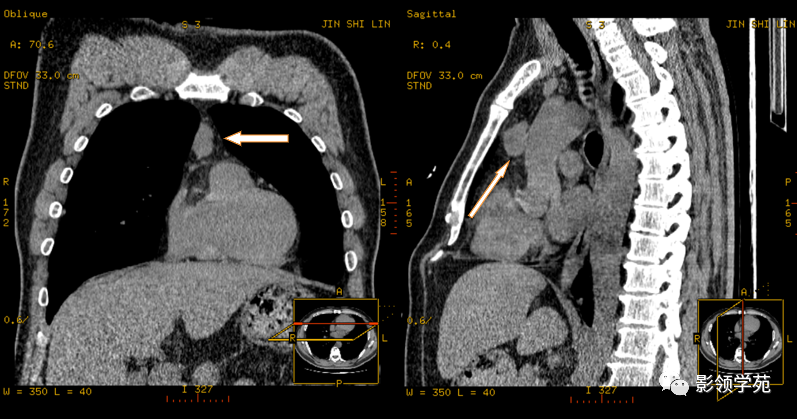

纵隔肿瘤的诊断主要依靠影像学检查,如X线、CT、MRI等。这些检查可以提供肿瘤的大小、部位、密度、成分以及与周围结构的关系等信息。对于疑似恶性肿瘤的患者,还可能需要进行活组织穿刺检查以明确诊断。